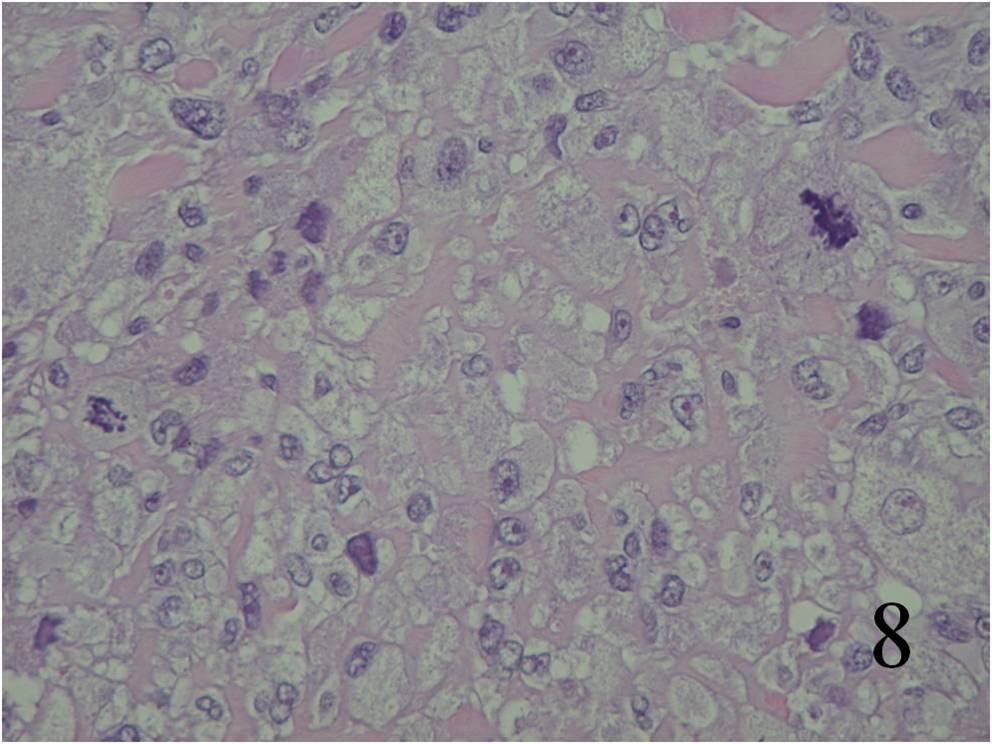

Large variation in differentiation, from obvious smooth muscle differentiation to an appearance similar to MFH (Fig. 7,8)

Fig. 7 Microscopic: Low and High (Fig. 8) power magnification of a leiomyosarcoma showing palisading spindle cells; with eosinophilic cytoplasm. Immunohistochemical stains for leiomyosarcoma are positive stain for actin (Fig. 9) and desmin (Fig. 10)